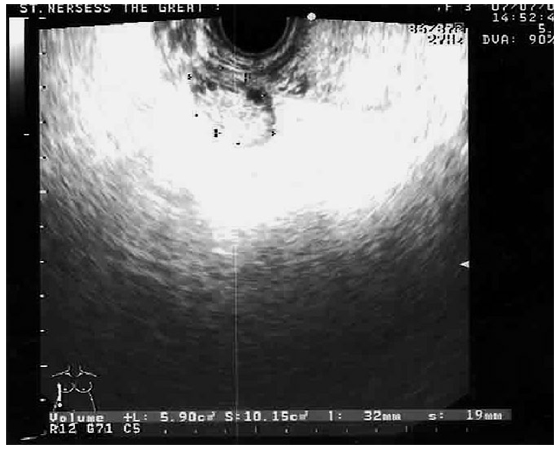

Следует отметить высокую частоту (58,9%) так называемой мелкокистозной дегенерации яичников у этих больных, которая была односторонней у 21,3% (25) пациенток и двусторонней – у 37,6% (44). Размер жидкостных образований варьировал от 0,9 до 1,4 см , в ряде случаев – с внутренней неоднородной взвесью (рис. 2).

Рис. 2. Эхограммы и схематическое изображение яичникa (мелкокистозная дегенерация): мелкокистозные включения от 0,9 до 1,4 см, повышение эхоплотности стромы без гиперплазии; локальные участки фиброза капсул

Объем стромального компонента яичника у этих больных (в отличие от ПКЯ) не превышал нормальных показателей, хотя эхоплотность стромы была повышенной. Уплотнение краевых отделов кортикального слоя яичников было выявлено у каждой 4-й, проявляясь локальными участками фиброза капсул, в чем и состояло отличие от процесса склерозирования у больных с ПКЯ. Присоединение периоофорита обусловливало нечеткую визуализацию краев яичника. Визуализация воспалительных изменений маточных труб, заключающихся в утолщении стенки трубы, значительно затрудняется при отсутствии жидкости в полости таза. Толщина воспаленной трубы, не содержащей жидкости в просвете, составляла около 10 мм. Еще одним признаком ХНСО, наблюдающимся у наших больных, была визуализация спаечного процесса в виде прямых (тонкие линейные гиперэхогенные образования, тянущиеся от матки к стенкам малого таза – при наличии свободной жидкости в полости таза) или косвенных (ретродевиация или латеральное отклонение матки, стойкая фиксация яичников, чаще всего позади матки) признаков.

Особо следует отметить, что в случаях аутоиммунного оофорита описанные изменения эхоструктуры яичников проявились в наиболее акцентированной форме – эхоплотность стромы яичников у этих больных была значительно повышена и сопоставима с эхоплотностью фиброзно измененных тканей. Особенно иллюстративными в этом отношении являются трансвагинальные эхограммы, которые дают возможность более наглядно визуализировать значительное повышение эхоплотности стромы (рис. 3).